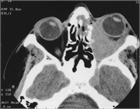

1. 多発血管炎性肉芽腫症(granulomatosis with polyangiitisGPA患者ではANCA(anti-neutrophil cytoplasmic antibodies)の陽性率は高い。腎症を伴う全身型の場合は80~90%で陽性である。また、頭頚部または肺のみに病変を認める限局型の場合は約60%で陽性である。したがって、GPAを疑う患者でのPR3-ANCA(c-ANCA)、MPO-ANCA(p-ANCA)測定は推奨される(推奨度1)